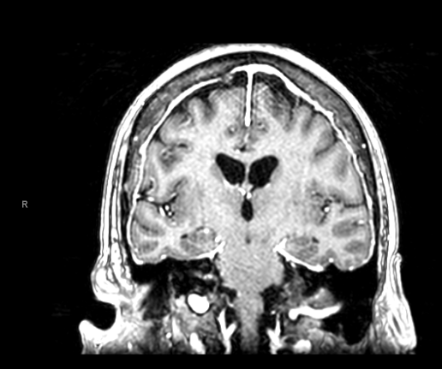

Case Presentation: A 49-year-old woman with a history of alcohol use disorder, hypertension, asthma, obesity, and prior lacunar stroke presented to a different hospital with seizure-like activity, encephalopathy, and right gaze deviation. Additional collateral history noted a year of progressive cognitive, bladder, and ambulatory dysfunction, resulting in wheelchair dependence.On admission, she was diagnosed with urosepsis from ESBL-producing Klebsiella pneumoniae, which was managed appropriately with IV antibiotics. However, she remained persistently encephalopathic. MRI of the neuraxis showed diffuse nodular leptomeningeal enhancement involving the brain and spinal cord. Lumbar puncture ruled out acute infectious meningitis and was negative for malignant cells but was notable for low glucose, elevated protein and elevated angiotensin-converting enzyme (ACE) levels in the CSF. No hilar lymphadenopathy or pulmonary infiltrates were noted on chest imaging. Empiric treatment for neurosarcoidosis involving intravenous immunoglobulins and high-dose glucocorticoids was started, resulting in rapid improvement in her encephalopathy. She was also noted to have central diabetes insipidus (CDI), characterized by high urine output (up to 9 L/day) and a positive water deprivation test. Leptomeningeal biopsy was negative for granulomas that characterize sarcoidosis, which was likely due to the recent receipt of high-dose steroids. Repeat CNS MRI showed resolution of leptomeningeal nodular enhancement but persistent cauda equina enhancement. She was discharged to a rehab facility on a prednisone taper, desmopressin, and infliximab.

Discussion: Our case describes a rare instance of presumed neurosarcoidosis presenting with diffuse leptomeningeal enhancement and CDI as its initial manifestation. CNS involvement in sarcoidosis is rare, affecting 5-15% of all patients with the disease. The subset of these cases involving the hypothalamus-posterior pituitary axis causing CDI is exceedingly rare, and its description is restricted to a few case reports.When evaluating a patient with neurological deficits and leptomeningeal enhancement on CNS imaging, it is important to consider infectious, inflammatory, and neoplastic etiologies. After infectious meningitis and cancer have been ruled out, it is vital to pursue a leptomeningeal biopsy early in the course of the illness if the diagnosis remains uncertain. Dramatic clinicopathological response to systemic steroids points strongly towards an inflammatory process. A thorough rheumatological evaluation should be undertaken to rule out common inflammatory diseases causing CNS involvement (e.g. RA, SLE, and vasculitides). CSF abnormalities in neurosarcoidosis are most pronounced in patients with diffuse leptomeningeal enhancement on MRI suggesting active disease. Improvement in CSF abnormalities may be a valuable tool for monitoring disease activity during therapy. Steroids combined with immunosuppressive drugs significantly improve response rates compared to steroids alone (69% vs. 35%). Radiation therapy to the CNS is an option for cases refractory to immunosuppression.